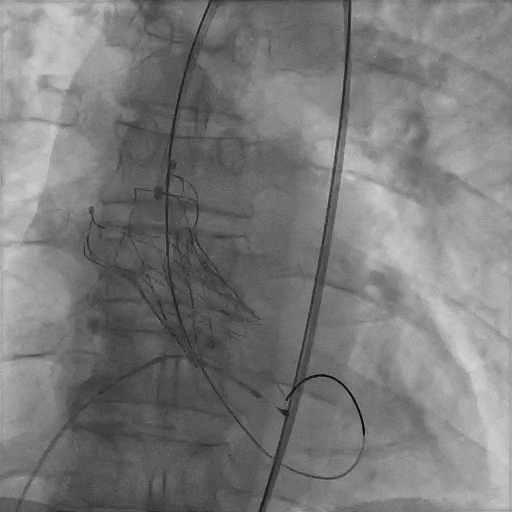

术中精彩操作

主动脉根部造影

导丝跨瓣

球囊预扩

瓣膜初始定位

瓣膜释放至工作体位

瓣膜完全释放,形态完美,无周漏